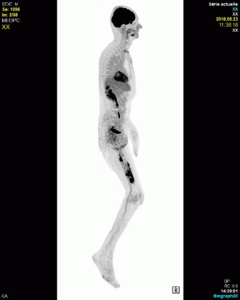

Le bilan d’extension TEP  est en faveur d’une atteinte lymphomateuse limitée au fémur gauche, sans autre atteinte à distance.

A noter un hypermétabolisme en périphérie de la PTH gauche peu spécifique dans le contexte de chirurgie récente, ainsi qu’un hypermétabolisme en région sus-claviculaire droite, au contact de la VVC, rapportée à sa pose récente.

Lymphome diffus à grandes cellules B de stade IE fémoral gauche.